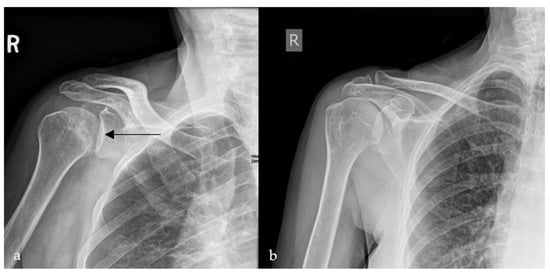

Cosmic Signs in Radiology: A Pictorial Review

Pattern recognition remains a cornerstone of radiologic interpretation, as it facilitates a confident and comprehensive differential diagnosis. Certain pathologies present with specific and highly recognizable patterns on imaging modalities. These patterns can resemble familiar real-life phenomena, including cosmic bodies that surround us. We present in this article a compilation of radiologic signs across various modalities that take inspiration from cosmic phenomena. For each sign, we summarize its defining imaging appearance, typical clinical context, and common pitfalls; where available, we note diagnostic performance (e.g., sensitivity/specificity) to guide appropriate weighting in practice. By coupling memorable imagery with succinct clinical guidance, this pictorial review aims to support a faster, more accurate pattern recognition that is applicable in both low-resource and tertiary care settings, while recognizing that these signs function as educational aids rather than validated diagnostic tests. In familiarizing themselves with these classic signs, training radiologists can benefit from an engaging and memorable way of recognizing various pathological conditions. Full article

Figure 1